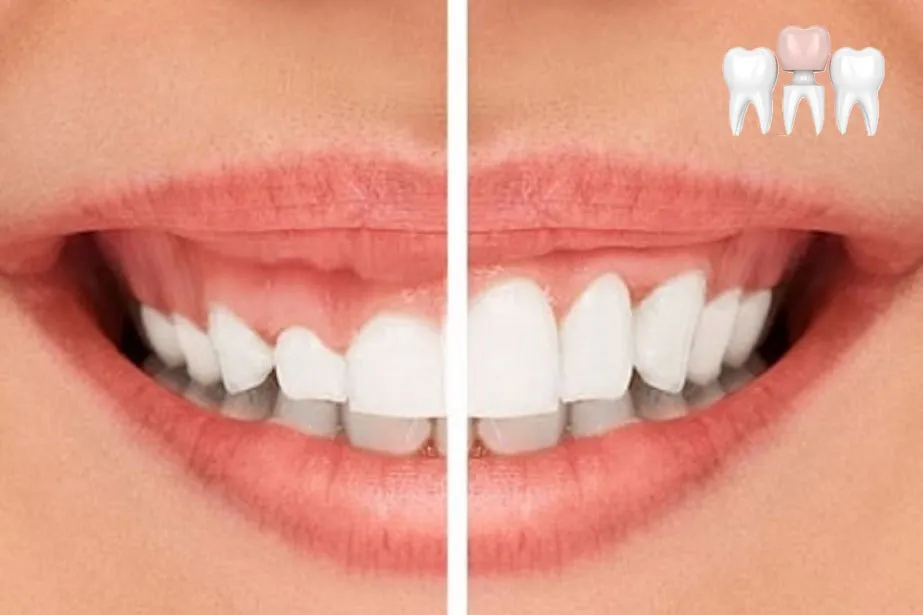

Một số trường hợp muốn bọc răng sứ nhưng điều kiện lợi không cho phép thực hiện. Lúc này, việc cắt lợi sẽ được thực hiện trước